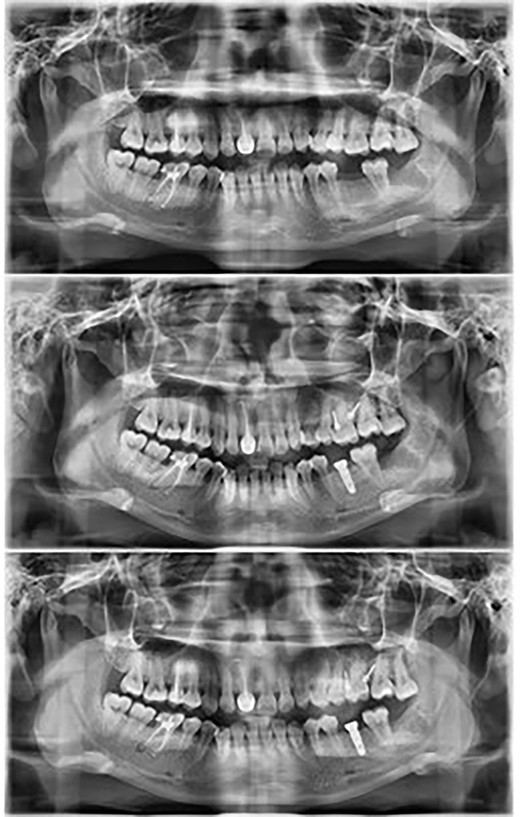

Following the placement of miniscrews, immediate loading was done with 100 g of intrusive force using a short power chain. The power chain was passed and engaged onto the composite button to ensure the forces are directed occlusally and there is no slippage. The patient was followed up at 4-week intervals and the power chain was replaced with one link, which was reduced at each appointment. After the first month, the dental implant was placed to replace the mandibular first molar. After 5 months of intrusion, the desired occlusal clearance was achieved and the upper and lower impressions were recorded (Fig. 2). For retention in the upper arch, the patient was given a clear vacuum retainer, while the crown was placed on the implant to prevent any relapse and to achieve good occlusion.

The intrusion process with placement of the prosthetic crown at the completion stage.

Maxillary molar intrusion 4 mm above the occlusal plane (Fig. 3).

Allowed for placement of full coverage crown on the implant placed to replace the mandibular first molar (Fig. 4).

Panoramic radiographs show the intrusion process along with placement of the implant in the opposing arch.